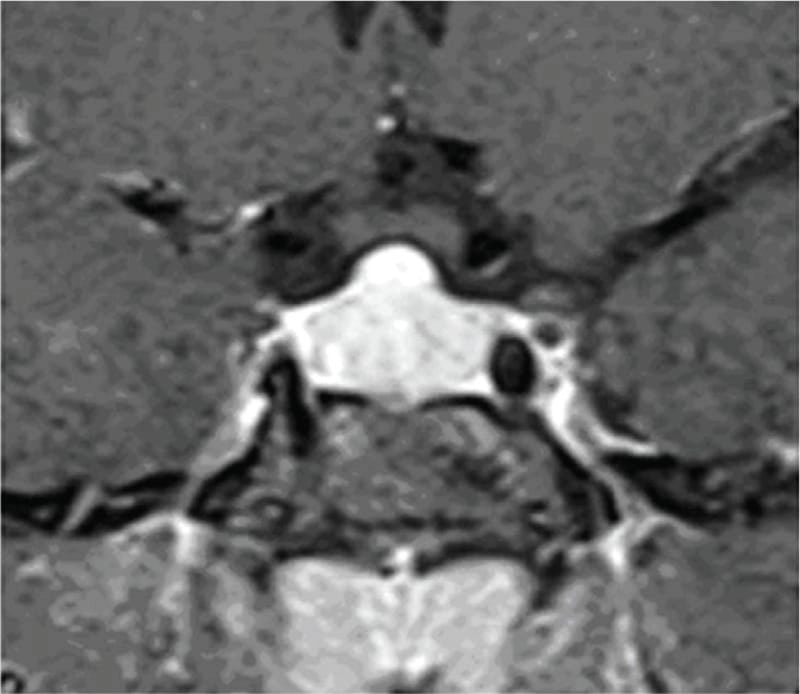

তবে পিটুইটারি হাইপারপ্লাসিয়া দেখা যায় প্রাইমারি গনাডাল, অ্যাডরিনাল বা হাইপোথাইরয়েডিজমের মত এন্ড অর্গান ইনসাফিসিয়েন্সিতে। বিশেষ করে, অব্যবহৃত প্রাইমারি হাইপোথাইরয়েডিজমে পিটুইটারি হাইপারপ্লাসিয়া পূর্বের ধারণার তুলনায় অনেক বেশি দেখা যায়। ২০১৯ সাল পর্যন্ত এরকম ১০৫টি কেস রিপোর্ট করা হয়েছে। এই ধরনের হাইপারপ্লাসিয়া গম্বুজ-আকৃতির (dome-shaped) হয়ে অপটিক কায়াজমাকে চেপে ধরতে পারে, যার ফলে অপারেশনের প্রয়োজন পড়তে পারে—যেমনটা আমাদের তৃতীয় কেসে ঘটেছিল।

চিকিৎসক তথা আবিষ্কারক সত্যম তিনটি কেসের বিষয় নিয়ে যখন তুলনা করতে নিলেন এবং পুরনো সৃষ্টি ঘাটতে শুরু করলেন তখন তিনি দেখতে পান সবগুলি ক্ষেত্রেই একই রকম সাদৃশ্য অর্থাৎ পিটুইটারি গ্রন্থি মাঝের অংশ এই গ্রন্থি দেখতে খানিকটা প্রজাপতির মতোই এবং তার মাঝের অংশের (প্রজাপতির দেহের উপরের অংশ মাথার মতই দেখতে) উপরের ভাগ সব ক্ষেত্রেই ডোমের মত বা গম্বুজ আকৃতির। তিনি এই ডোম বা গম্বুজ আকৃতি হওয়ার কারণ বিশ্লেষণ করতে গিয়ে দেখেন পিটুইটারির সামনের অংশ যেখানে থাইরোট্রপগুলো থাকে, যেখান থেকে এই টিউমারটি হয়। আর যখনই এটি বাড়বে তখন টমের মতনই তৈরি হবে। অর্থাৎ গম্বুজ আকৃতির। আর সেখান থেকেই ডোম-সাইনের উৎস অর্থাৎ আবিষ্কার।

MRI-তে এই হাইপারপ্লাসিয়া সাধারণত গম্বুজ-আকৃতির ও সমমিত হয় এবং হোমোজেনাস সিগনাল ইন্টেনসিটি দেখায়, যেখানে সাধারণ নন-ফাংশনাল পিটুইটারি অ্যাডেনোমা নানা আকার ও অসমতা নিয়ে দেখা যায়।

পূর্ববর্তী গবেষণাগুলিও এই ‘Dome Sign’-এর গুরুত্ব তুলে ধরেছেন, যেমন ডঃ আহমেদ (১৯৮৯), ডঃ সারলিস (২০০০), ডঃ ফ্রান্সেস্কি ও পাসেরি (২০১১) এবং ডঃ শুক্লা (২০১৯)। এসব গবেষণায় MRI-তে ডোম-আকৃতির হাইপারপ্লাসিয়া শণাক্ত হয়েছে যা লেভোথাইরক্সিন চিকিৎসার মাধ্যমে কয়েক সপ্তাহের মধ্যেই হ্রাস পেয়েছে।

তাঁর দাবি, MRI-তে ‘DOME Sign’ থাকা এবং TSH বাড়তি থাকলে, সেটি হাইপোথাইরয়েডিজম-জনিত হাইপারপ্লাসিয়ার সম্ভাবনার কথা নির্দেশ করে এবং এই রোগীদের শুধুমাত্র লেভোথাইরক্সিন দিয়ে চিকিৎসা করলে পূর্ণ আরোগ্য সম্ভব।